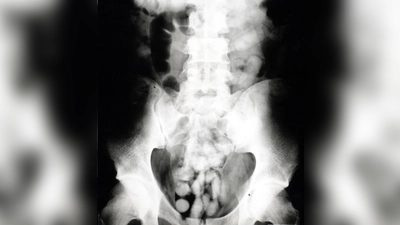

Bei der Zollkontrolle verstrickte sich kürzlich ein Mann, der aus Brasilien nach Großbritannien reisen wollte, am Flughafen in Widersprüche. Ein angeordneter Drogenwischtest zeigte Kokain. Da sich beim Kolumbianer kein Kokain fand, musste er im Krankenhaus geröntgt werden. 90 Schluckbehältnisse („Bodypacks”) kamen bei dem 36-Jährigen zum Vorschein. „Das Röntgenbild zeigte Fremdkörper und bestätigte den Verdacht”, so Pressesprecherin Marie Müller. Das Verschlucken von Drogen zum Transport wird als Bodypacking bezeichnet. Drogen werden dazu in speichel- und magensäureresistente Beutel verpackt. Platzt nur einer, bedeutet das meist den Tod. Es wurde Haftbefehl erlassen, weitere Ermittlungen laufen.